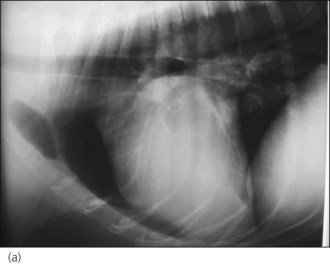

Pleural effusion is common in cats with CHF but this is rarely due to right-sided failure alone and the exact mechanism remains unclear. The nature of the pleural effusion may vary (modified transudate, pseudochylous, chylous) and heart failure is the most common cause of chylothorax in cats. Most cats have bilateral or left-sided disease and pulmonary oedema is usually present, even if it is harder to detect due to the pleural effusion (Figure 31.3).

Figure 31.3 Right lateral thoracic radiographs of a cat with congestive heart failure; cardiomegaly and pulmonary oedema are present.